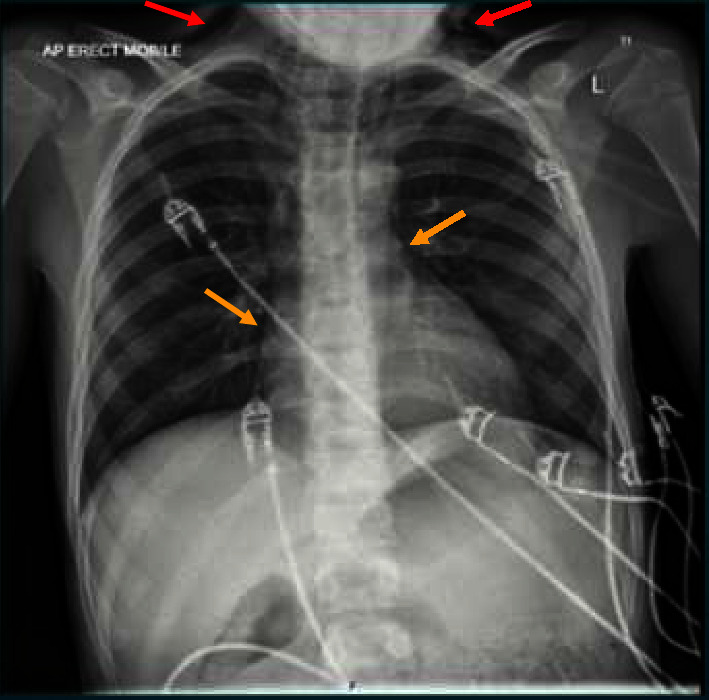

哈曼氏综合征是糖尿病酮症酸中毒(DKA)的一种罕见并发症,以皮下气肿和自发性气胸为特征。本病例报告讨论了一名新诊断为 1 型糖尿病(T1DM)并伴有严重 DKA 的 11 岁男性青少年发生哈曼氏综合征的情况。患者表现出典型的 DKA 症状,包括多尿、多饮、腹痛和乏力,同时伴有脱水、库氏呼吸和心动过速等体征。经过静脉输液和胰岛素输注等初步治疗后,他被转到一家三级儿童医院接受进一步治疗。随后,在常规检查中,他表现出双侧颈部吱吱作响,听诊时纵隔有嘎吱声,这表明他患有哈曼氏综合征。保守治疗后症状缓解,患者出院并安排了后续治疗。本病例强调了识别哈曼氏综合征作为儿童患者 DKA 潜在并发症的重要性。及时诊断和处理,并与 Boerhaave's 综合征等更严重的疾病区分开来,对于确保良好的预后至关重要。进一步认识和了解这种罕见的综合征对于优化患者护理和管理至关重要。

Hamman's syndrome, a rare complication of diabetic ketoacidosis (DKA), is characterized by subcutaneous emphysema and spontaneous pneumomediastinum. This case report discusses the occurrence of Hamman's syndrome in an 11-year-old adolescent male newly diagnosed with type 1 diabetes mellitus (T1DM) and presenting with severe DKA. The patient exhibited symptoms typical of DKA, including polydipsia, polyuria, abdominal pain, and fatigue, alongside signs such as dehydration, Kussmaul breathing, and tachycardia. Following initial management with intravenous fluids and insulin infusion, he was transferred to a tertiary children's hospital for further care. Subsequently, on routine examination, he exhibited bilateral neck crepitus and a mediastinal crunching sound on auscultation, indicative of Hamman's syndrome. Conservative management led to symptom resolution, and the patient was discharged with follow-up arranged. This case highlights the importance of recognizing Hamman's syndrome as a potential complication of DKA in pediatric patients. Prompt diagnosis and management, along with differentiation from more severe conditions like Boerhaave's syndrome, are crucial for ensuring favorable outcomes. Further awareness and understanding of this rare syndrome are essential for optimal patient care and management.